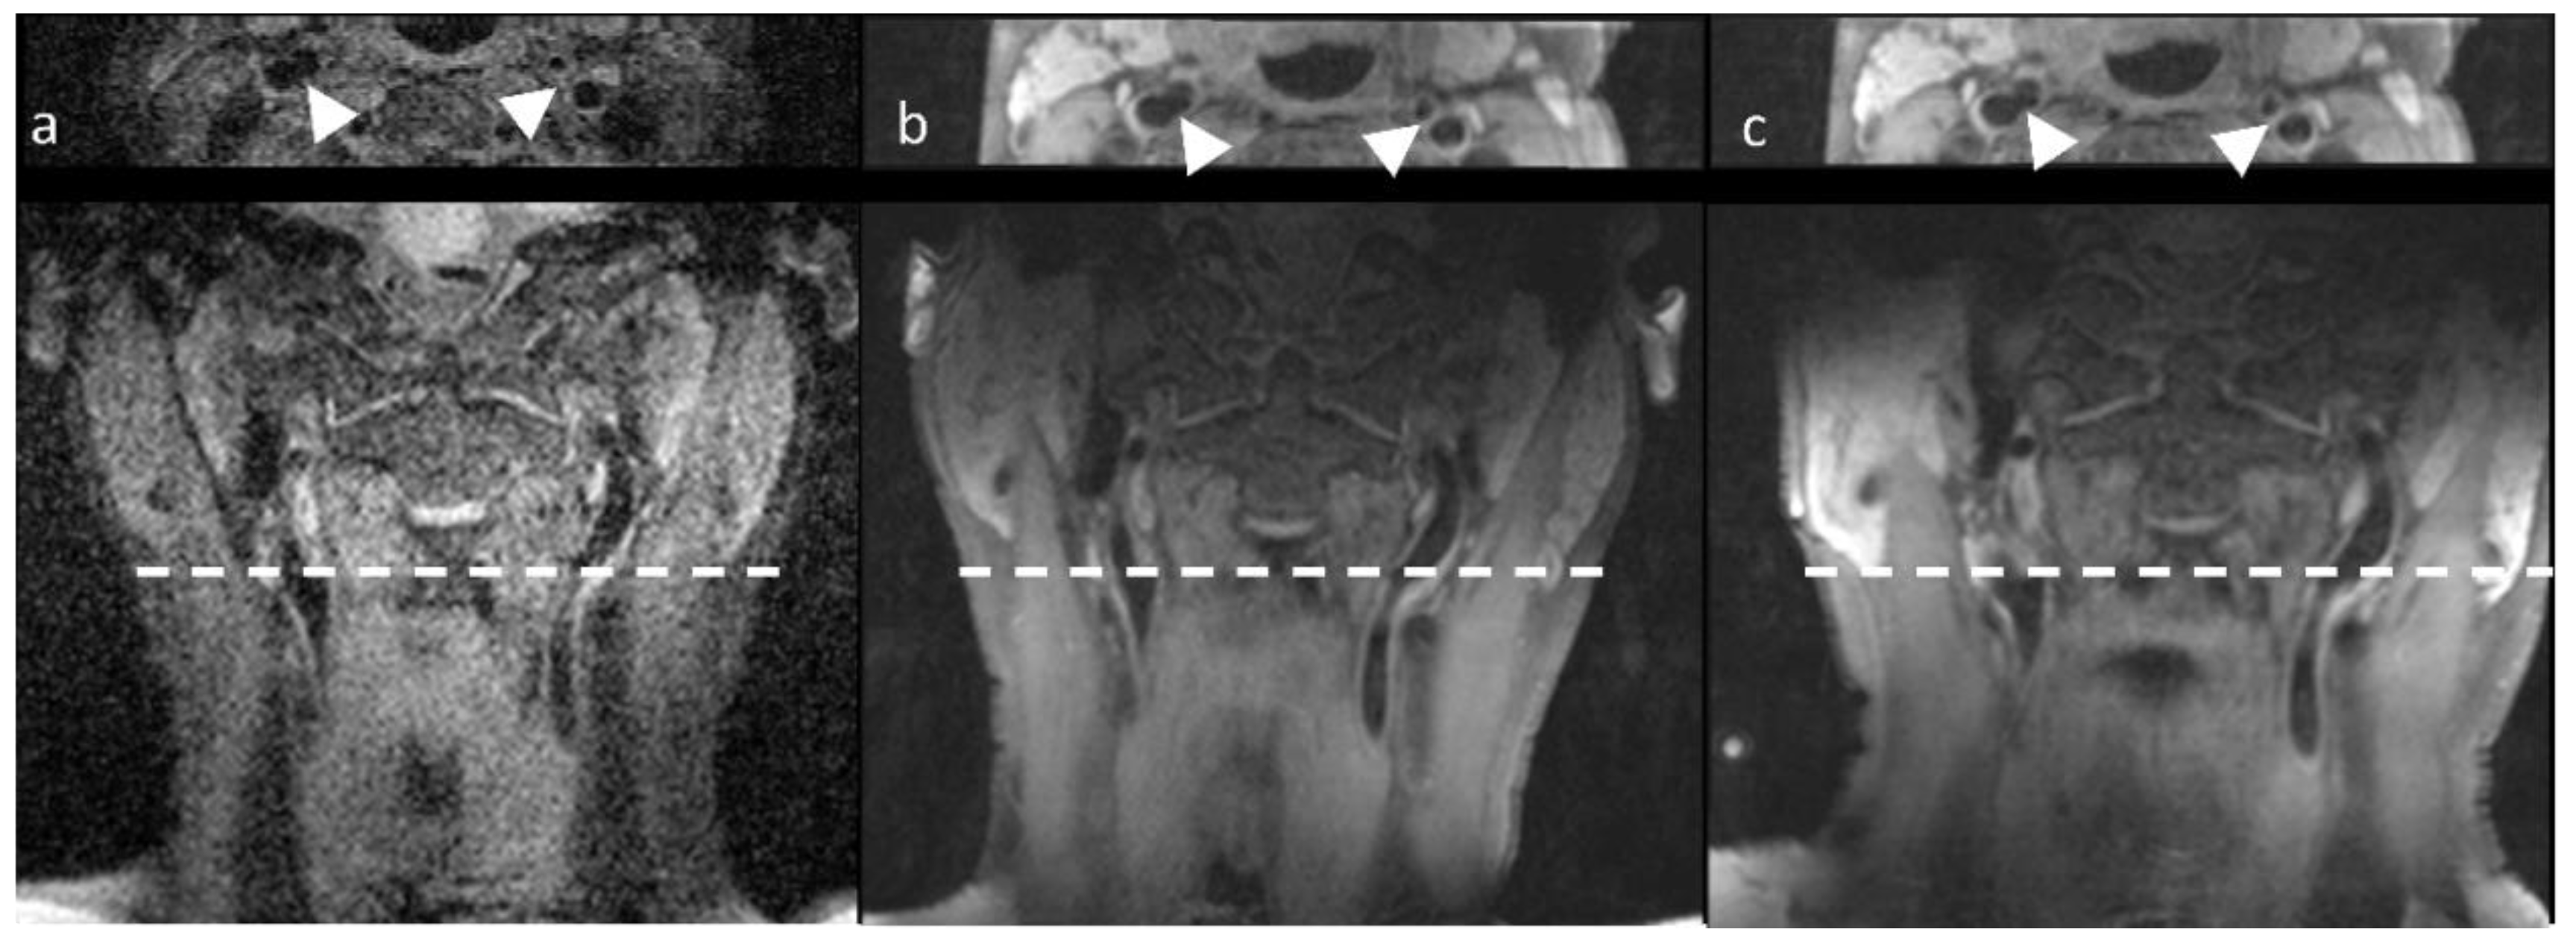

3.2. Patient Study